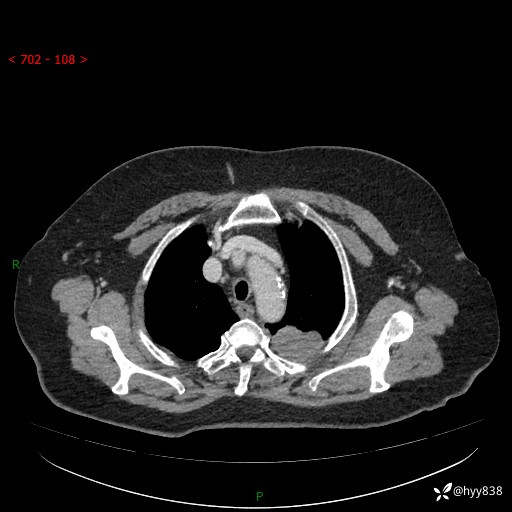

老年女性,左上肺结节8年。典型又不典型,看你如何解读---结果公布(值得分析)

主诉:检查发现左上肺结节8年,较前增大。

简要病史:患者于8年前体检行胸部CT检查发现左上肺结节(4mm),患者平素间断咳嗽咳痰,无心慌、胸闷、胸痛、呼吸困难、低热、盗汗,无头痛、头晕,无腹痛、腹胀等不适,未行特殊处理,定期复查。2023-09-21胸部CT示左上肺结节(2cm)较前增大,2024-02-01胸部CT示左上肺尖后段(39*32mm),左侧肺门及纵隔淋巴结增大,现患者欲求手术治疗,遂来我院就诊,以“左上肺结节”收入我科。 患者自起病以来,精神可,睡眠可,饮食可,大小便正常,体重无明显改变。

辅助检查:CT

胸部CT平扫

增强(动脉期+静脉期)